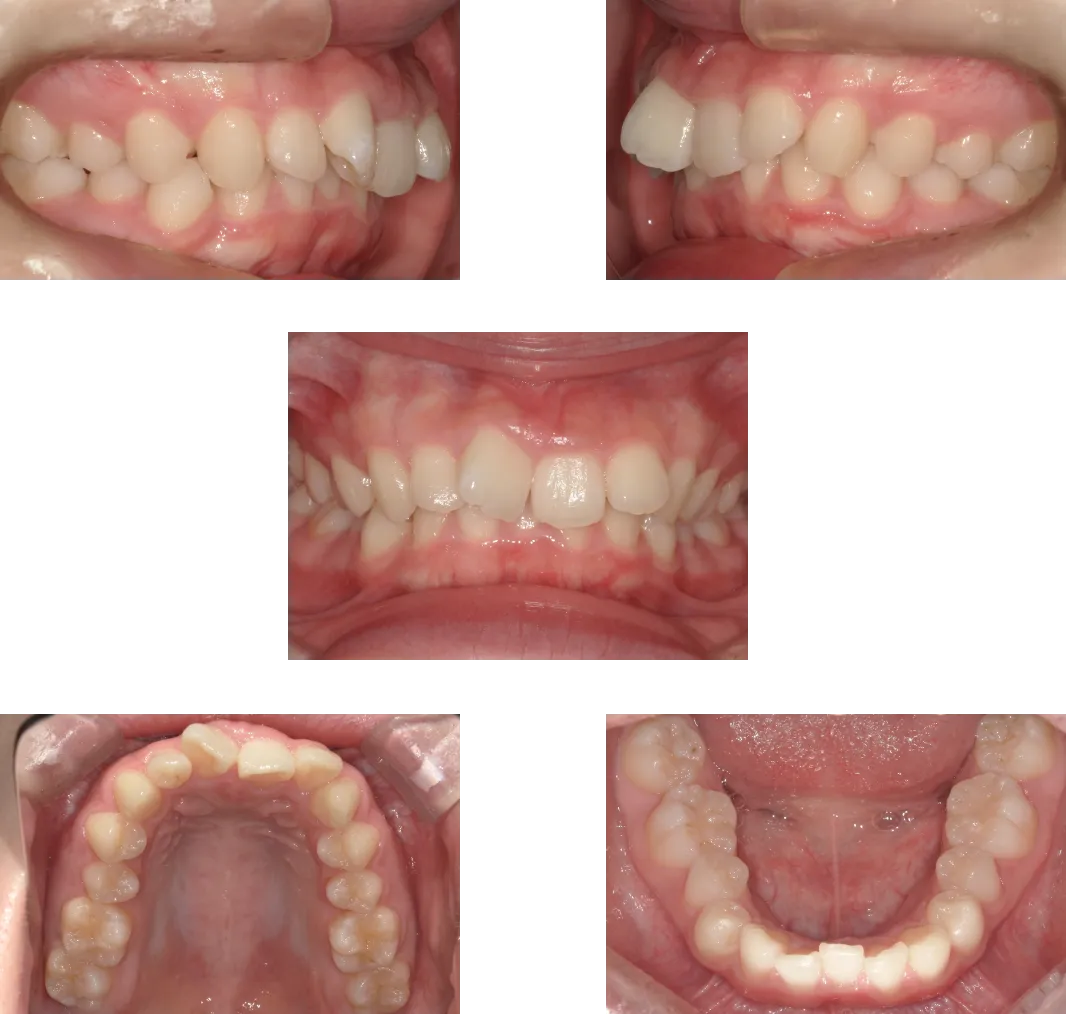

過蓋咬合 -20歳-

• Before

• After

診断

叢生、骨格性上顎前突

治療期間

1年6ヶ月+保定期間2年

料金

1,070,000円

抜歯

なし

リスク

痛み、軽度の歯根吸収、術後の変化